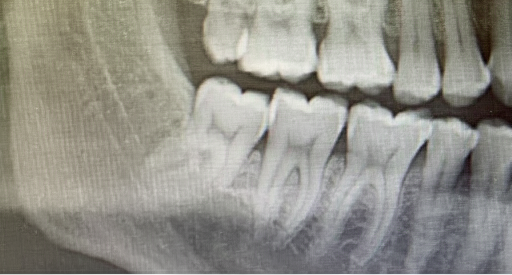

![]() |

| Remove wisdom teeth. | 0.6/0.7/0.8 | 0.5/0.4/0.8 | 0.7/0.6/0.4 | 0.2/0.1/0.8 | 0.7/0.6/0.5 | 0.0/0.2/0.5 | 0.2/0.6/0.8 | |

Each row includes the previous and ground truth images, followed by outputs from seven models. Scores below each output denote EA (Editing Accuracy), VQ (Visual Quality), and CP (Masked SSIM) (all in [0, 1] range).